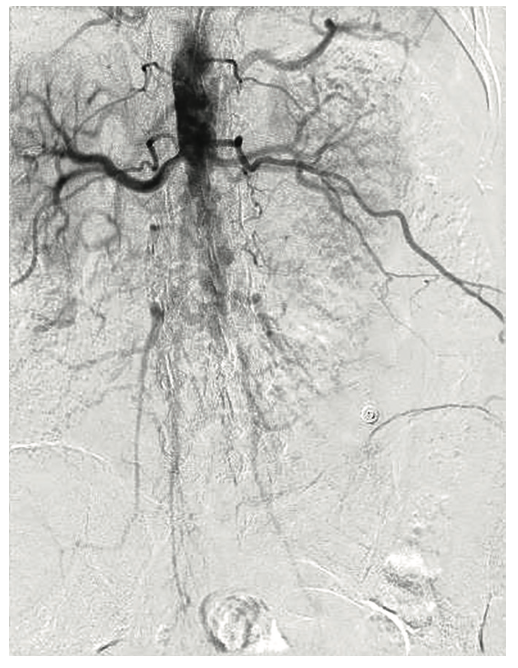

A 54-year-old female with a history of peripheral arterial disease (PAD), tobacco abuse, diabetes, severe chronic obstructive pulmonary disease (COPD), obesity, hypertension, and hyperlipidemia presented to an outside hospital with a non-ST-elevation myocardial infarction (NSTEMI). Subsequent left heart catheterization revealed a chronic total occlusion (CTO) of the left anterior descending coronary artery (LAD) and left circumflex (LCx), with a 95% ostial ramus and a patent right coronary artery (RCA) with right to left collaterals (Figures 1-2). Initial ejection fraction by ventriculogram was approximately 30-35%. She was turned down for surgery and subsequent studies revealed viable myocardium; therefore, she was scheduled for percutaneous revascularization with mechanical circulatory support using an Impella left ventricular assist device (Abiomed). She was found to have bilateral occlusion of her iliac stent (Figure 3). It was decided to revascularize at least one of her occluded iliac arteries, and then use the femoral and radial approach for dual access in order to recanalize the CTO. The axillary artery would be used for the Impella, rather than advancing the 14 French (Fr) sheath through a freshly stented artery. The right iliac artery was revascularized and she was brought back to revascularize the left system.

The right groin was accessed using fluoroscopic guidance. A micropuncture sheath was placed and upsized to a 7 French, 45 cm Destination sheath (Terumo) in the right groin. We accessed the right radial, but could not get good flow. Therefore, we ended up using the ulnar artery with ultrasound guidance and placed a Terumo 5/6 Slender sheath in the ulnar artery. We proceeded to access the left axillary artery. We placed a Judkins right (JR)4 catheter in the left subclavian and did a selective angiogram, documenting the location of the thoracoacromial artery and circumflex humeral (Figure 4); then using a Chiba biopsy needle (Cook), accessed the axillary artery and placed a 5-French 30 cm sheath (Cook)(Figure 5). We used the 15 cm biopsy needle to allow us a shallow angle of approach with the patient’s body habitus and to avoid “kinking” the sheath. We then switched out for the Lunderquist wire (Cook Medical), placed an 8 Fr sheath, and performed a pre-close using two Perclose devices (Abbott Vascular) (Figure 6).